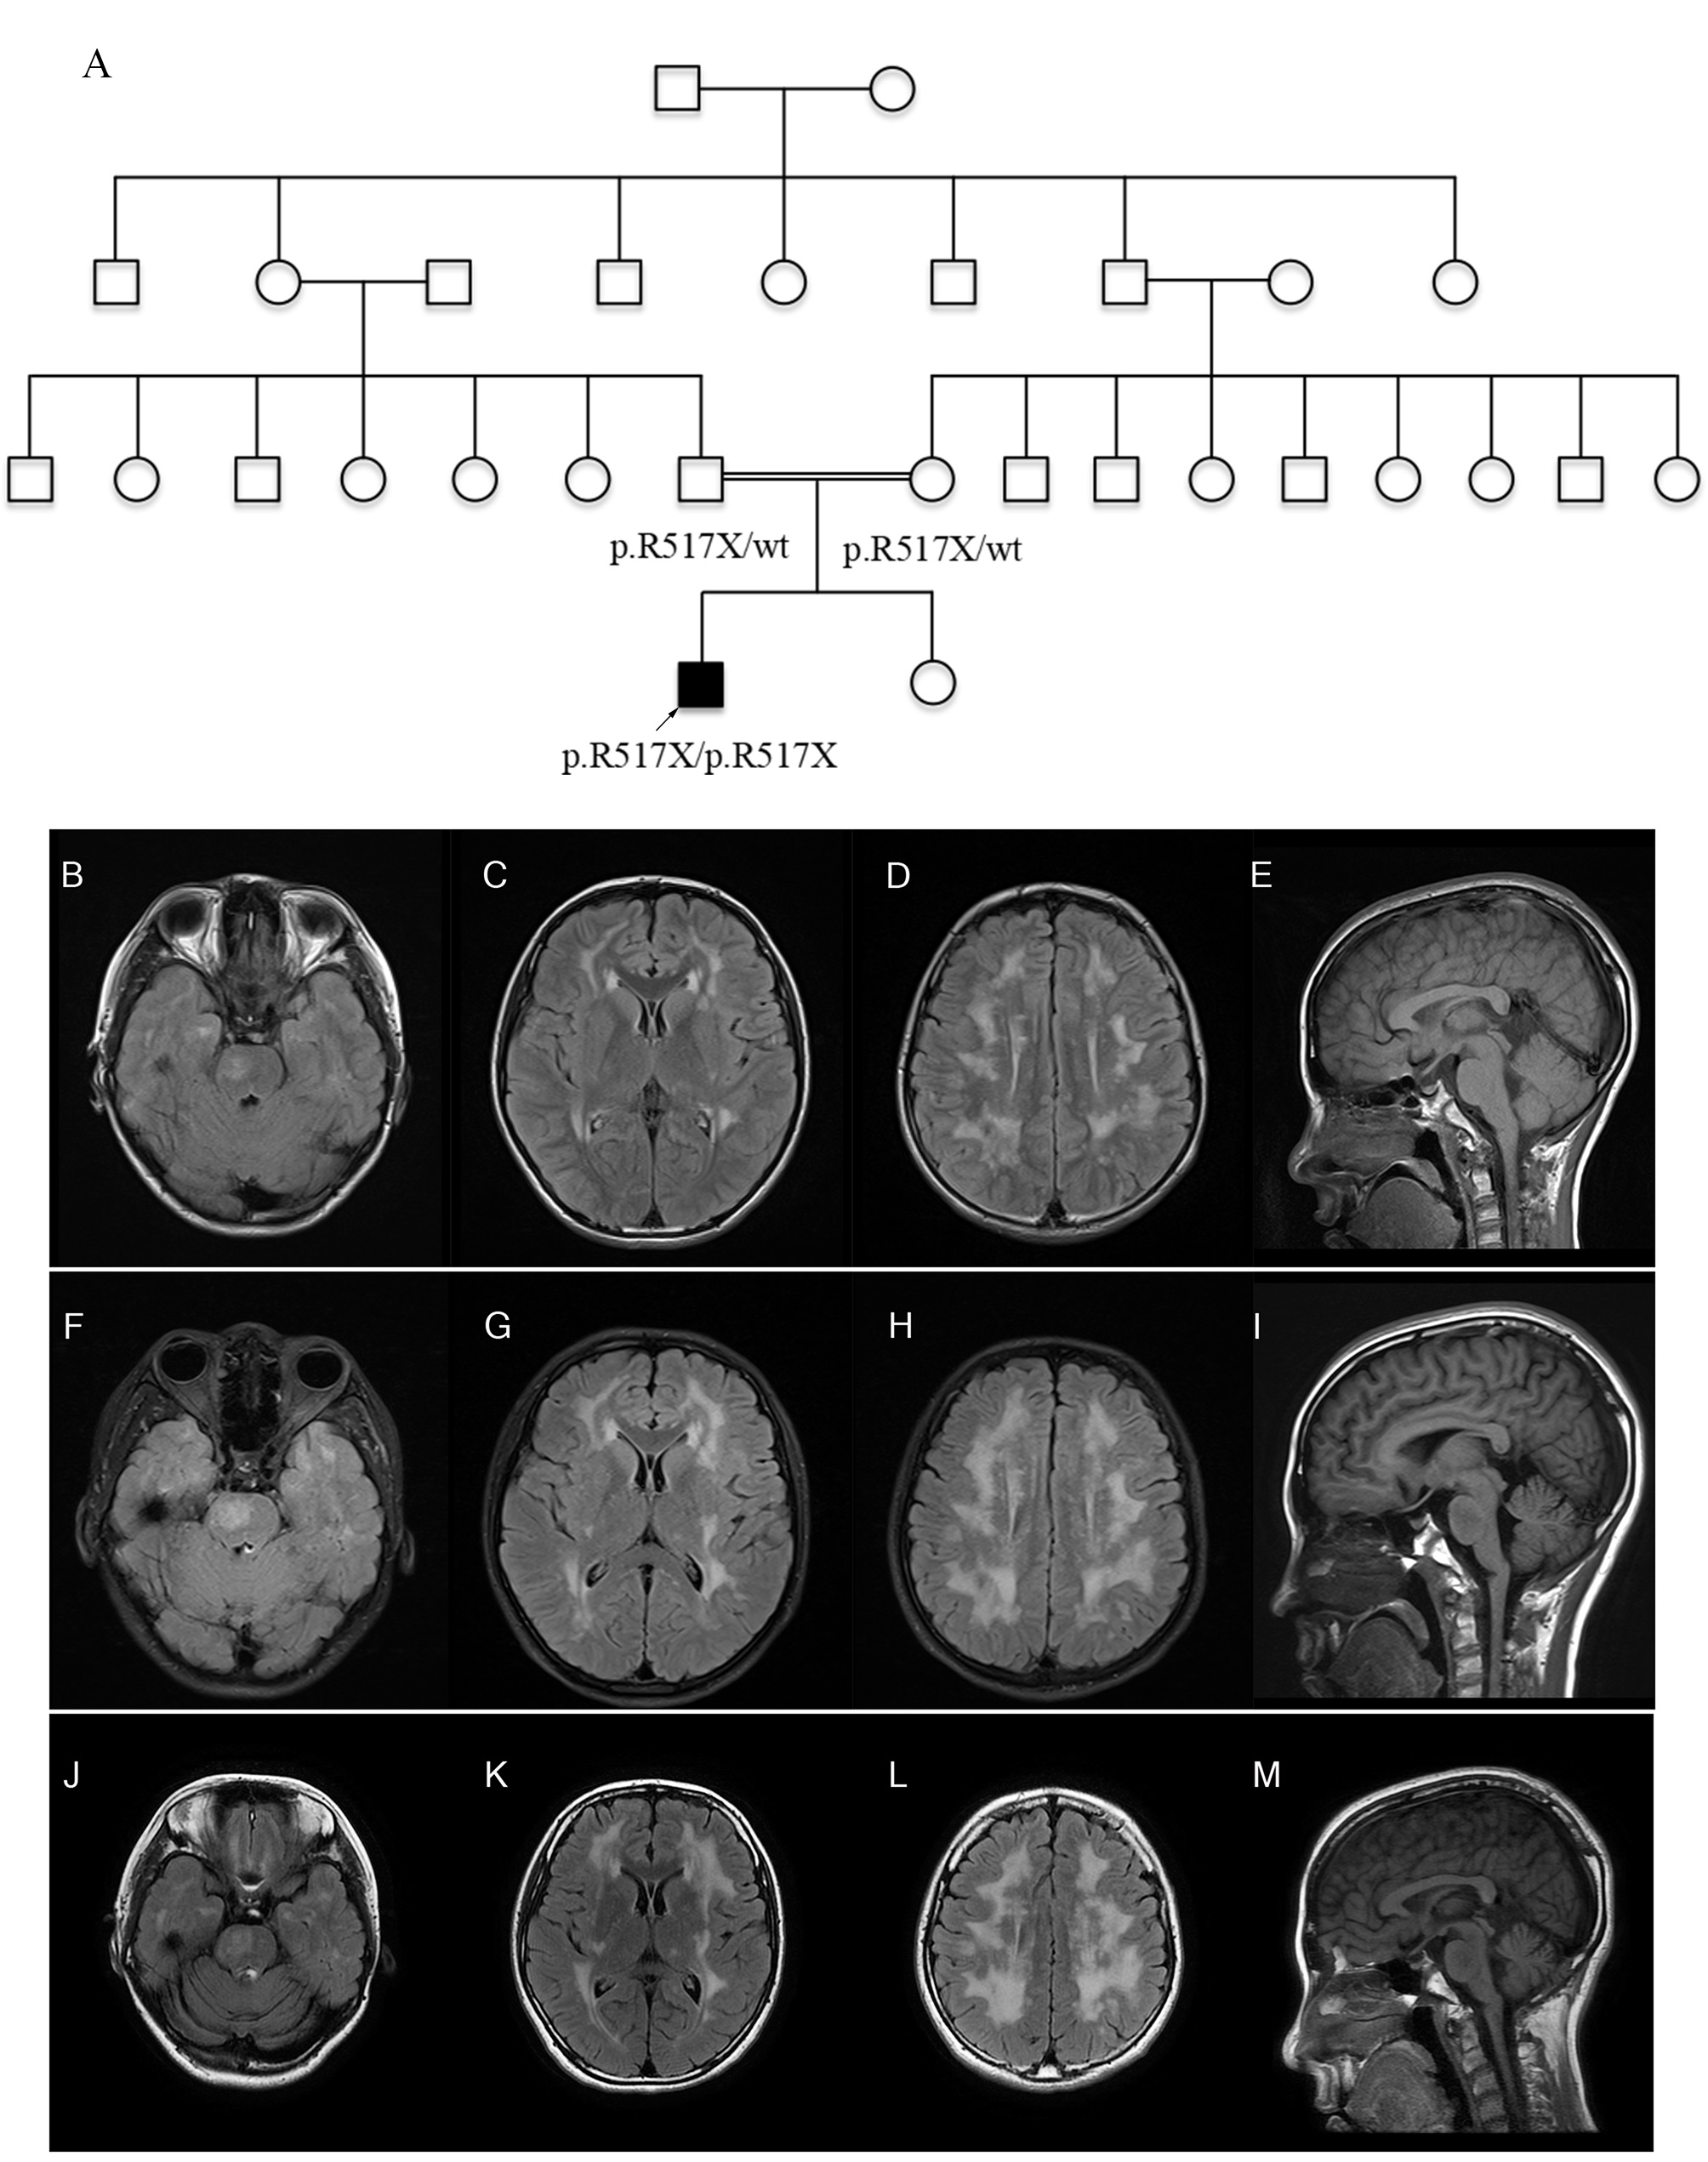

RNF216-related disorder is a rare neuroendocrine disease resulting from RNF216 gene mutations with diverse symptoms and inheritance pattern. This study reported a new case with a novel causative RNF216 variant and reviewed all individuals with causative RNF216 variants in previous reports. We found that ataxia was the most frequent initial symptoms in individuals under 30 years old, while chorea was the most frequent initial symptom in individuals over 30 years old. Over 90% of individuals presented with cognitive impairment and hypogonadotropic hypogonadism throughout the disease. Furthermore, the majority of RNF216 variants affect the RBR domain or C-terminal extension. (https://jmg.bmj.com/content/early/2023/11/27/jmg-2023-109397 )

Clinical and genetic spectrum of RNF216-related disorder: A new case and literature review (Contributed by Dr. Chujun Wu)